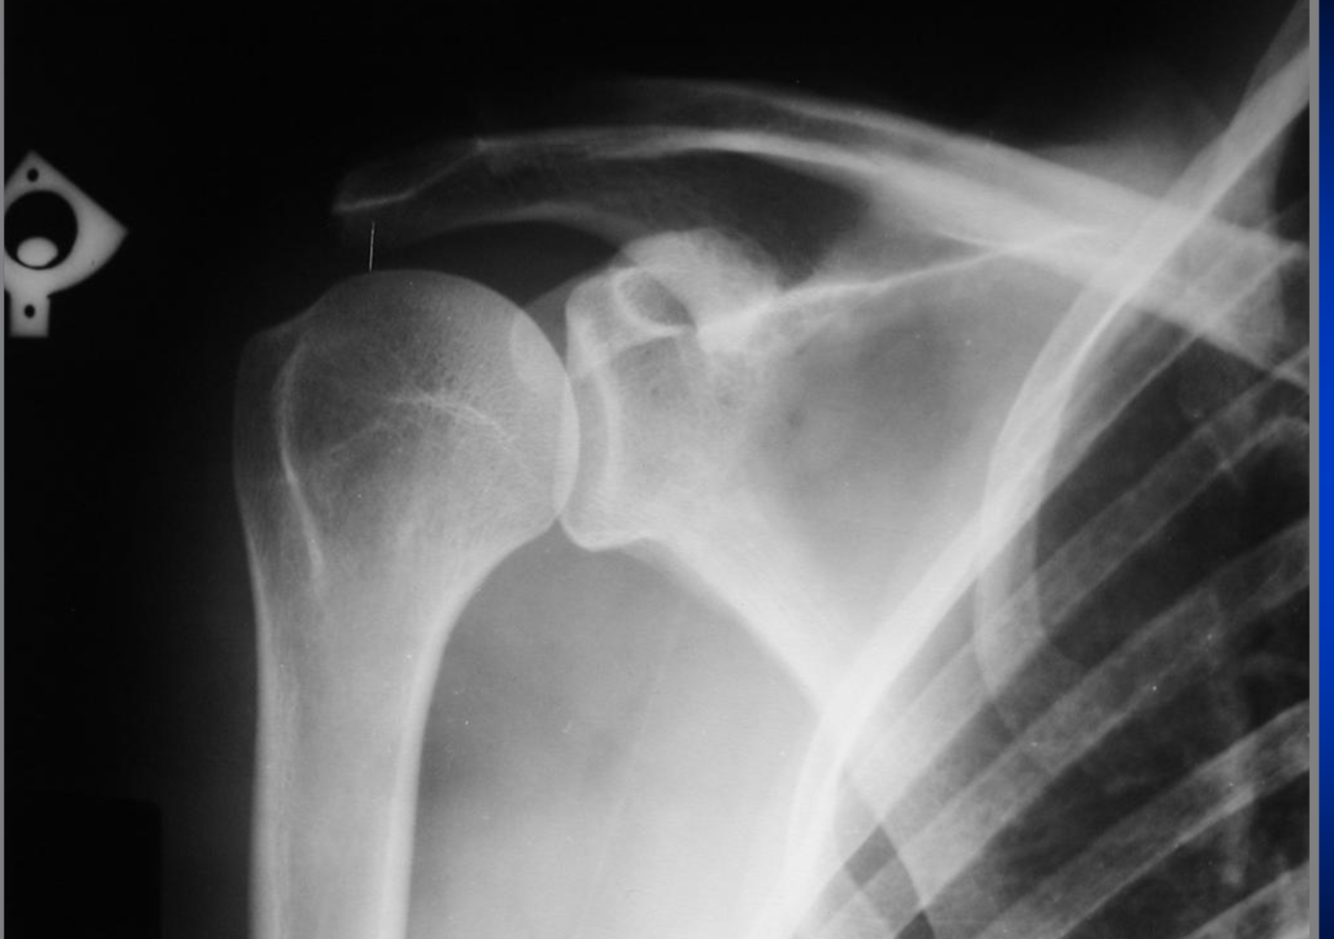

AP External Rotation Shoulder

rotation int car le trochin médiale et tochiter plus lat

rot int de l”paule G car trochin et trochiter sont écarté

positionnnement articulation gléno huméral visible

B technique ok et desité ok

on voit le processus coracoide G

épine

acrominon

glénoide G

cartilage :

glénoidal ou scapulo huméral

acromioclaviculaire